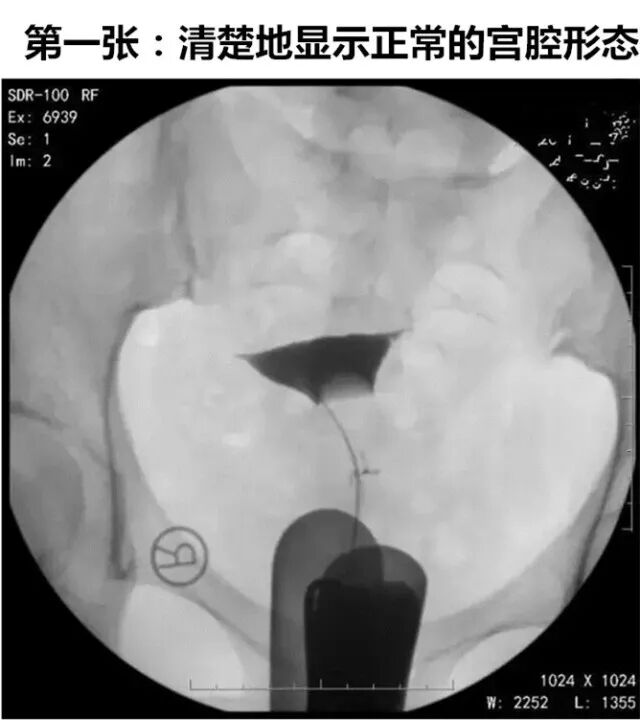

实时动态子宫输卵管碘油造影是将传统的造影改良,使患者无痛,将球囊导管置入宫颈内口,注入液体充盈球囊堵住宫颈内口后,将碘化油经导管缓慢注入宫腔,在X光透视下,动态观察碘油逐渐膨胀宫腔,流入输卵管,经伞端流入盆腔的全过程。在操作后的12~24小时,再拍一张延迟涂抹片,观察碘油在盆腔内的弥散情况。

延迟涂抹片就是在造影操作后(如造影剂用的是碘油,则为术后12-24小时,如造影剂用的是碘水,则为术后10-40分钟内),在盆腔再照一张X光片,观察盆腔内碘油弥散情况。

如下图所示,这是一张正常的延迟涂抹片,碘油在盆腔内均匀弥散。